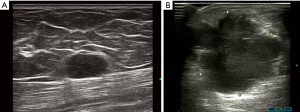

In our study, the maximum size of breast lesions in 6 cases ranged from 1.2 to 4.5 cm, and 1 case with a diffused breast lesion was identified (Figure 1). The shape of breast metastases in 5 (5/7, 71.4%) cases was irregular, with the other 2 (2/7, 28.6%) cases having an oval shape (Figure 2). The margin of metastases in 6 (6/7, 85.7%) cases was indistinct, while in the remaining case the margin was noted to be well circumscribed. The lesions were hypoechoic in all cases (7/7, 100.0%) and had heterogeneous internal echogenicity in 5 (5/7, 71.4%) cases, while homogeneous internal echogenicity was found in 2 (28.6%) cases. The lesion orientation of 6 (6/7, 85.7%) cases was parallel (wider than tall), 3 (3/7, 42.9%) cases showed enhancement posterior feature (Figure 3), and 1 (1/7, 14.3%) case had a feature of posterior acoustic shadowing. Microcalcification was not observed in any patient. Color Doppler US detected blood flow in 2 (2/7, 28.6%) cases. Associated secondary signs, including edema and skin thickening, were found in 5 (5/7, 71.4%) cases. The final BI-RADS assessment categories were BI-RADS 3 in 1 (1/7, 14.3%) case, BI-RADS 4A in 1 (1/7, 14.3%) case, BI-RADS 4B in 1 (1/7, 14.3%) case, BI-RADS 4C in 3 (3/7, 42.9%) cases, BI-RADS 5 in 1 (1/7, 14.3%) case.

The common US features of primary breast cancer are irregular, not parallel, indistinct, irregular, hypoechoic, homogeneous masses with microcalcification and posterior acoustic shadowing (19). The common US features of breast metastases from lung cancer are nodules that are irregular, indistinct, hypoechoic, and parallel masses without calcification. The maximum size of breast metastases from lung adenocarcinoma was larger than that of large cell and small cell lung cancer. In addition, internal echogenicity was homogeneous in patients with large cell and small cell lung cancer, while it was heterogenous in patients with adenocarcinoma. Most lesions were parallel to the skin. Posterior acoustic enhancement was also observed in our study. This is different from the US feature of primary breast cancer, where posterior acoustic shadowing is most typical (20). However, we still observed 1 patient with a diffused breast metastasis featuring posterior acoustic shadowing, which, to our knowledge, is the first report of these features in breast metastases. Calcification, which is rarely observed in metastasis to the breast, may be helpful in distinguishing stage IV disease from a primary breast cancer. Only 1 prior study has reported a case of calcifications in lung cancer metastatic to the breast (13). Color blood flow signal was detected in 2 patients, which is different from the abundant vascularity of primary breast carcinoma (21). Sippo et al. (20) and Moreno-Astudillo et al. (22) reported that the US manifestation of other cancer metastases to the breast were round or oval hypoechoic lesions, which could be diagnosed as benign nodules. This study also observed a case of metastatic small cell lung cancer to the breast, which demonstrated an oval shape and indistinct margin, and homogeneous internal echogenicity. In contrast, Luh et al. (23) reported 2 small lung cancer masses with a distinct margin and heterogeneous internal echogenicity.